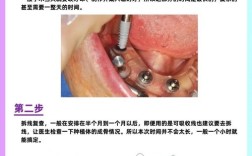

- 影像学指导: 术前必须拍摄CBCT(锥形束CT),这是精确测量骨头高度、宽度、评估骨密度、定位重要解剖结构的必要工具,医生在CBCT上精确规划种植体的植入位置、深度和角度。

- 拍摄CBCT。